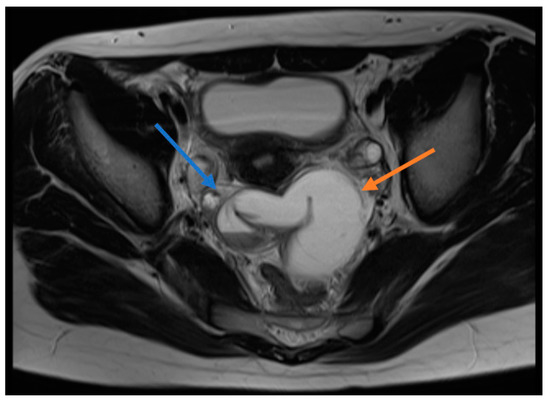

Nine of the patients underwent surgery on the day of admission. One patient was operated on four days later after further examinations were performed due to non-relieving pain, previous abdominal pain attacks and the detection of a paraovarian solid mass on USG. Two patients were operated on using the laparoscopic technique, while eight underwent open surgery. Torsioned tubes were equal on both sides. Five patients did not have any additional intervention because of normalized blood supply after detorsion, while the other five patients underwent a cystectomy/salpingectomy (Figure 2). The pathological examination of the resected material revealed changes such as chronic salpingitis along with serosal cysts (Table 2).

Figure 2.

Isolated fallopian tube torsion material caused by hydrohematosalpinx.